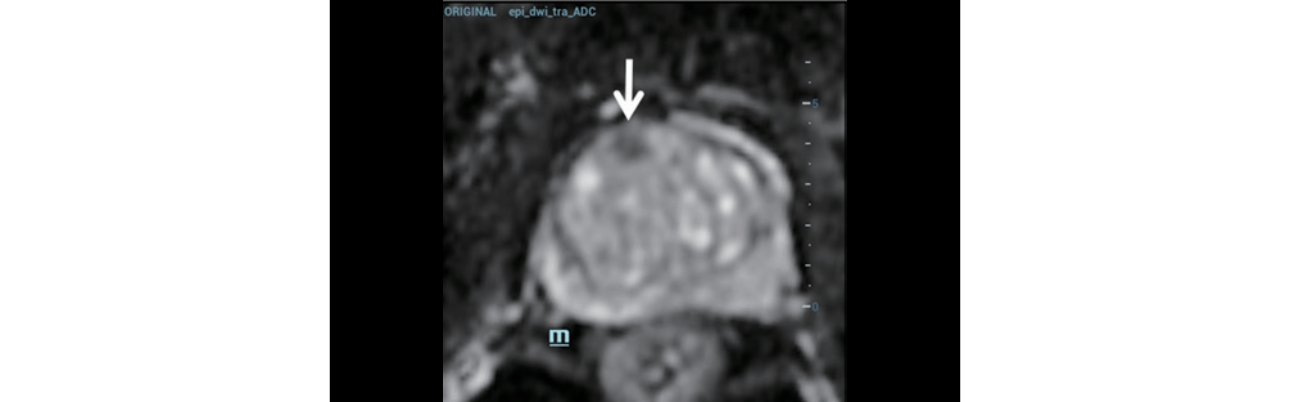

Step 3: 병변의 위치를 파악하기 위해 해부학적 참고가 되는 MRI 영상(Figure 5)을 사용하여 조영제 증강 초음파(CEUS)를 실시했습니다.

trus-mri-fusion-fig5-pc

형상5. 조영제 증강 초음파에서는 MRI에서 보인 병변에 해당하는 부위가 반대쪽의 말초 조직 대비 초기 증강을 보여줌.